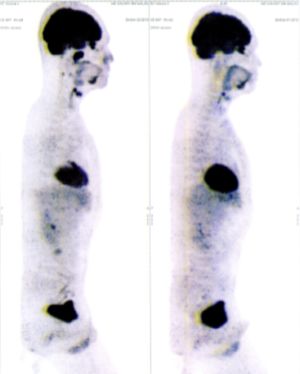

CASE NO: 1 - A FEW MONTHS LATER

A few months after successful treatment for hepatocellular carcinoma, and partially successful for stomach cancer, the PET/CT scan showed the stomach cancer becoming very active, with several metastases to the parts of the liver not previously involved by hepatocellular carcinoma. After a few treatment, all the active stomach cancer lesions in the stomach and in the liver went into remission.